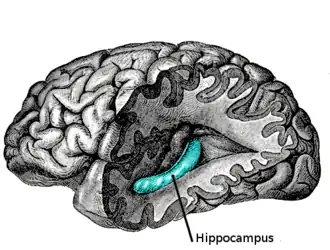

Humans have two hippocampi, one in each hemisphere of the brain. They are located in the medial temporal lobe of the brain. In this lateral view of the human brain, the frontal lobe is at the left, the occipital lobe at the right, and the temporal and parietal lobes have largely been removed to reveal one of the hippocampi underneath. | |